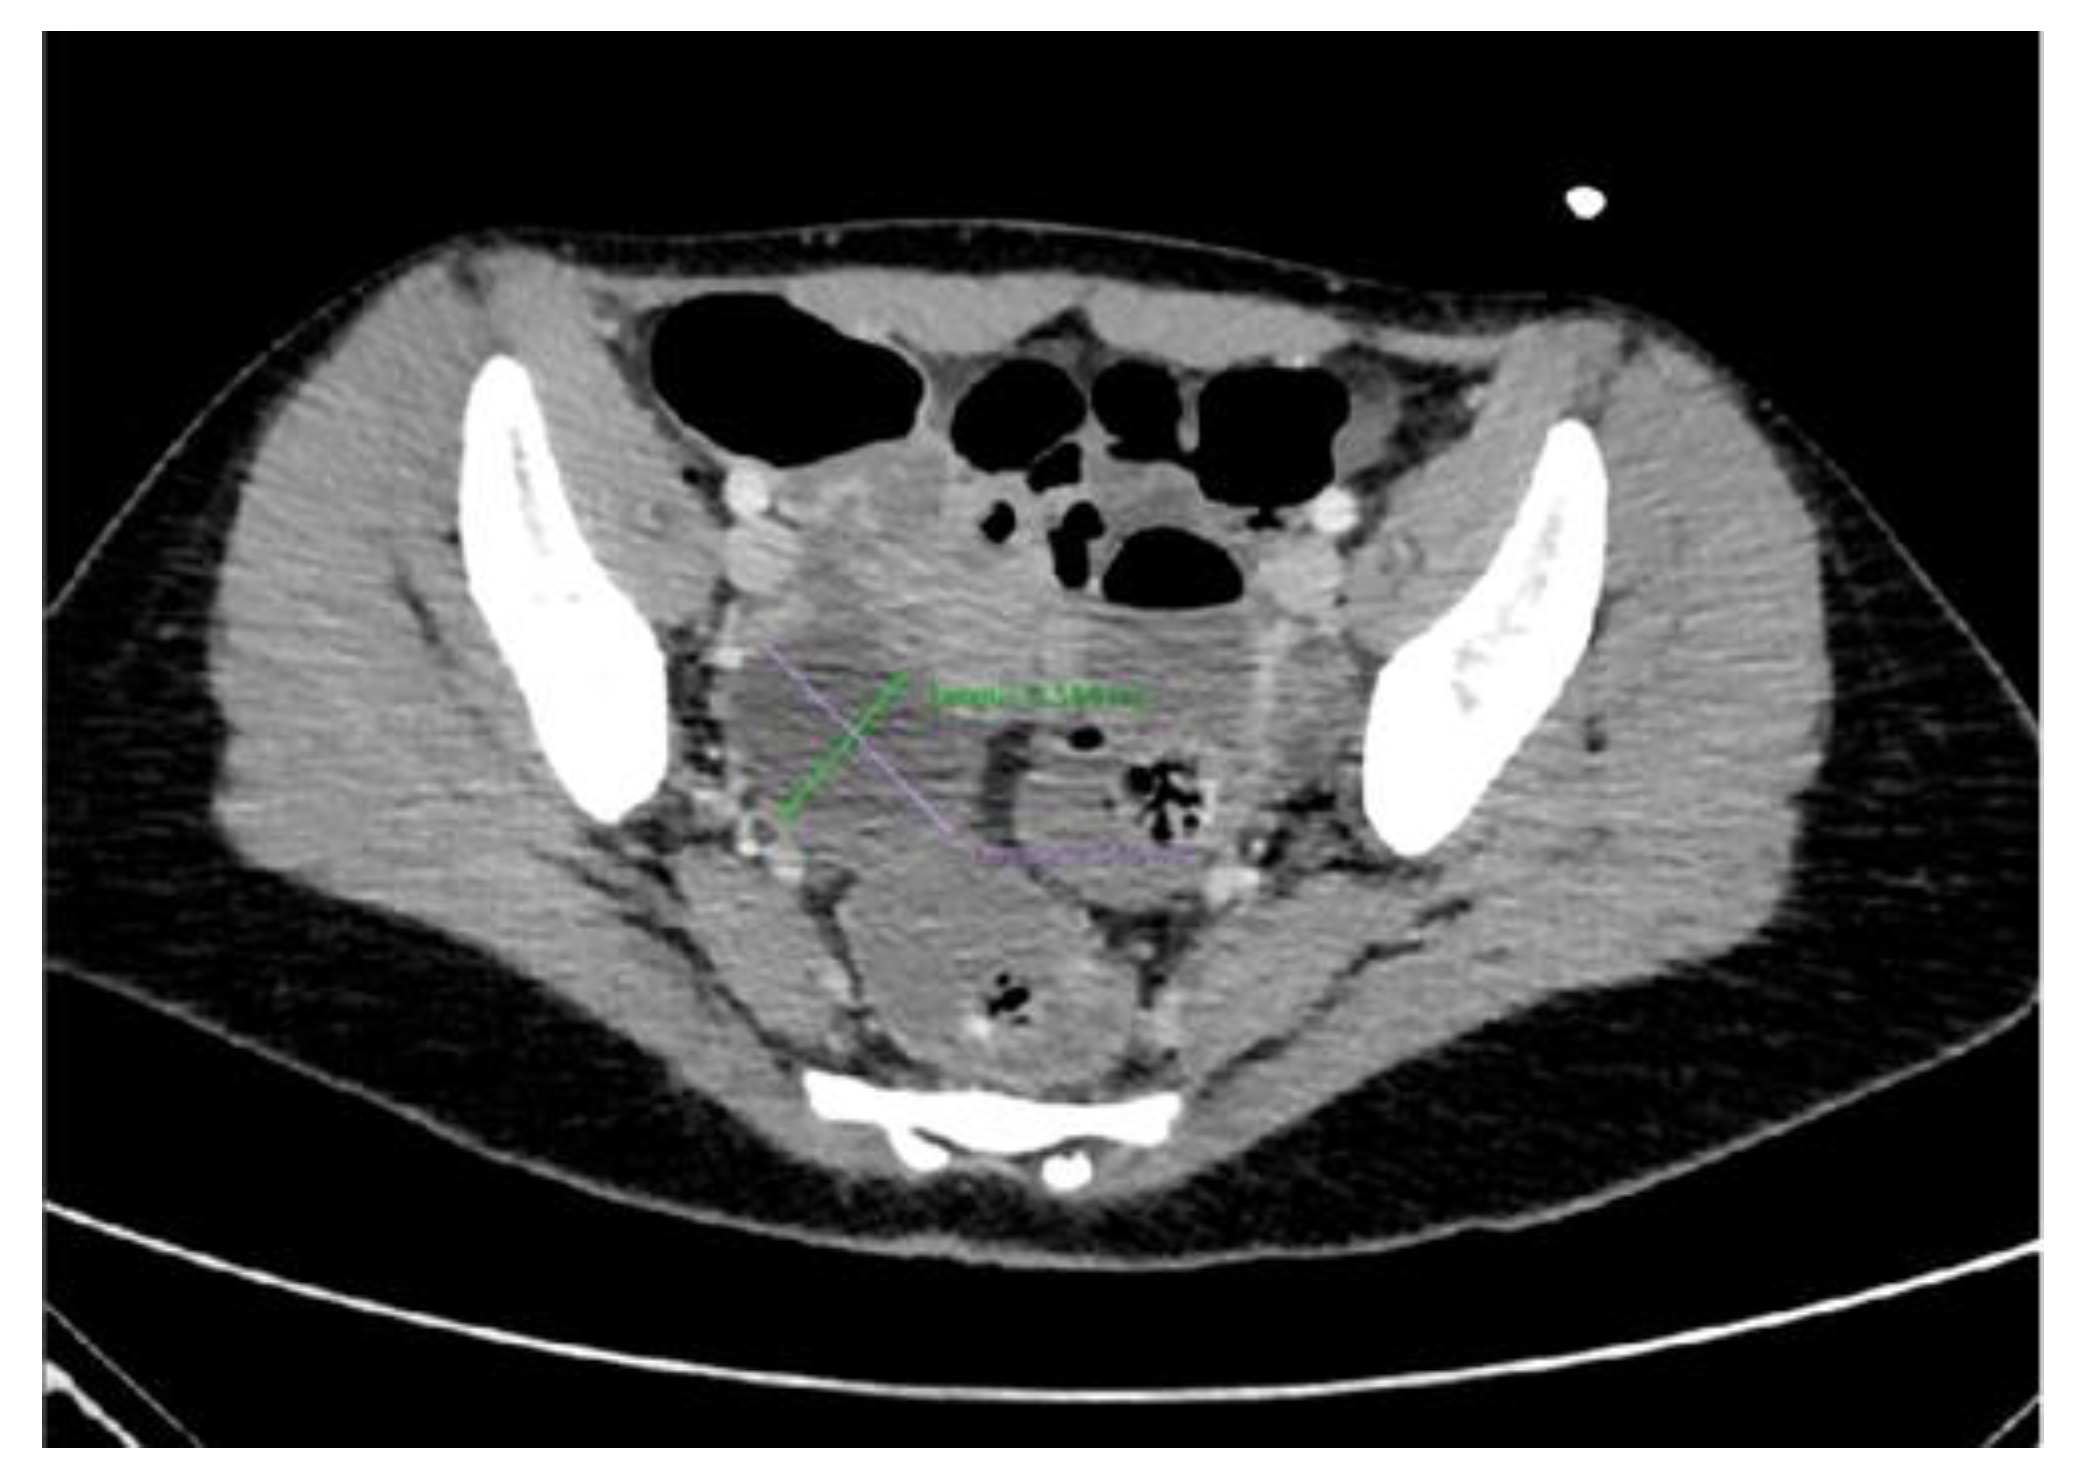

| Single cystic lesion with an echogenic nodule that leads to acoustic shadowing | Unilocular cyst with various septa and a prominent raised protuberance called “Rokitansky nodule”, containing calcifications |

| “Tip of the iceberg” sign, due to markedly echogenic areas with posterior acoustic shadowing | A marked acoustic shadowing masks the true extent of the teratoma due to presence of an echogenic focus, resulting from the presence of hair, cellular debris, fat, teeth, and calcifications |

| “Comet tail” sign | Shadowing without an echogenic focus at the tip, due to the presence of hair balls |

| Fat–fluid and fluid–fluid levels | Different echogenicity between liquid fluid, fat, and sebum |

| “Dot–dash” sign due to hyperechoic lines and dots | Different orientation of floating hair within the cyst, appearing as dots when perpendicular to the imaging plane, and dashes when parallel |

| Highly echogenic avascular mass | Poor vascularization and high presence of fat, hair, and calcifications |

| “Meat/floating balls” sign | Floating hyperechoic balls, composed of sebum, keratin, and hair balls |